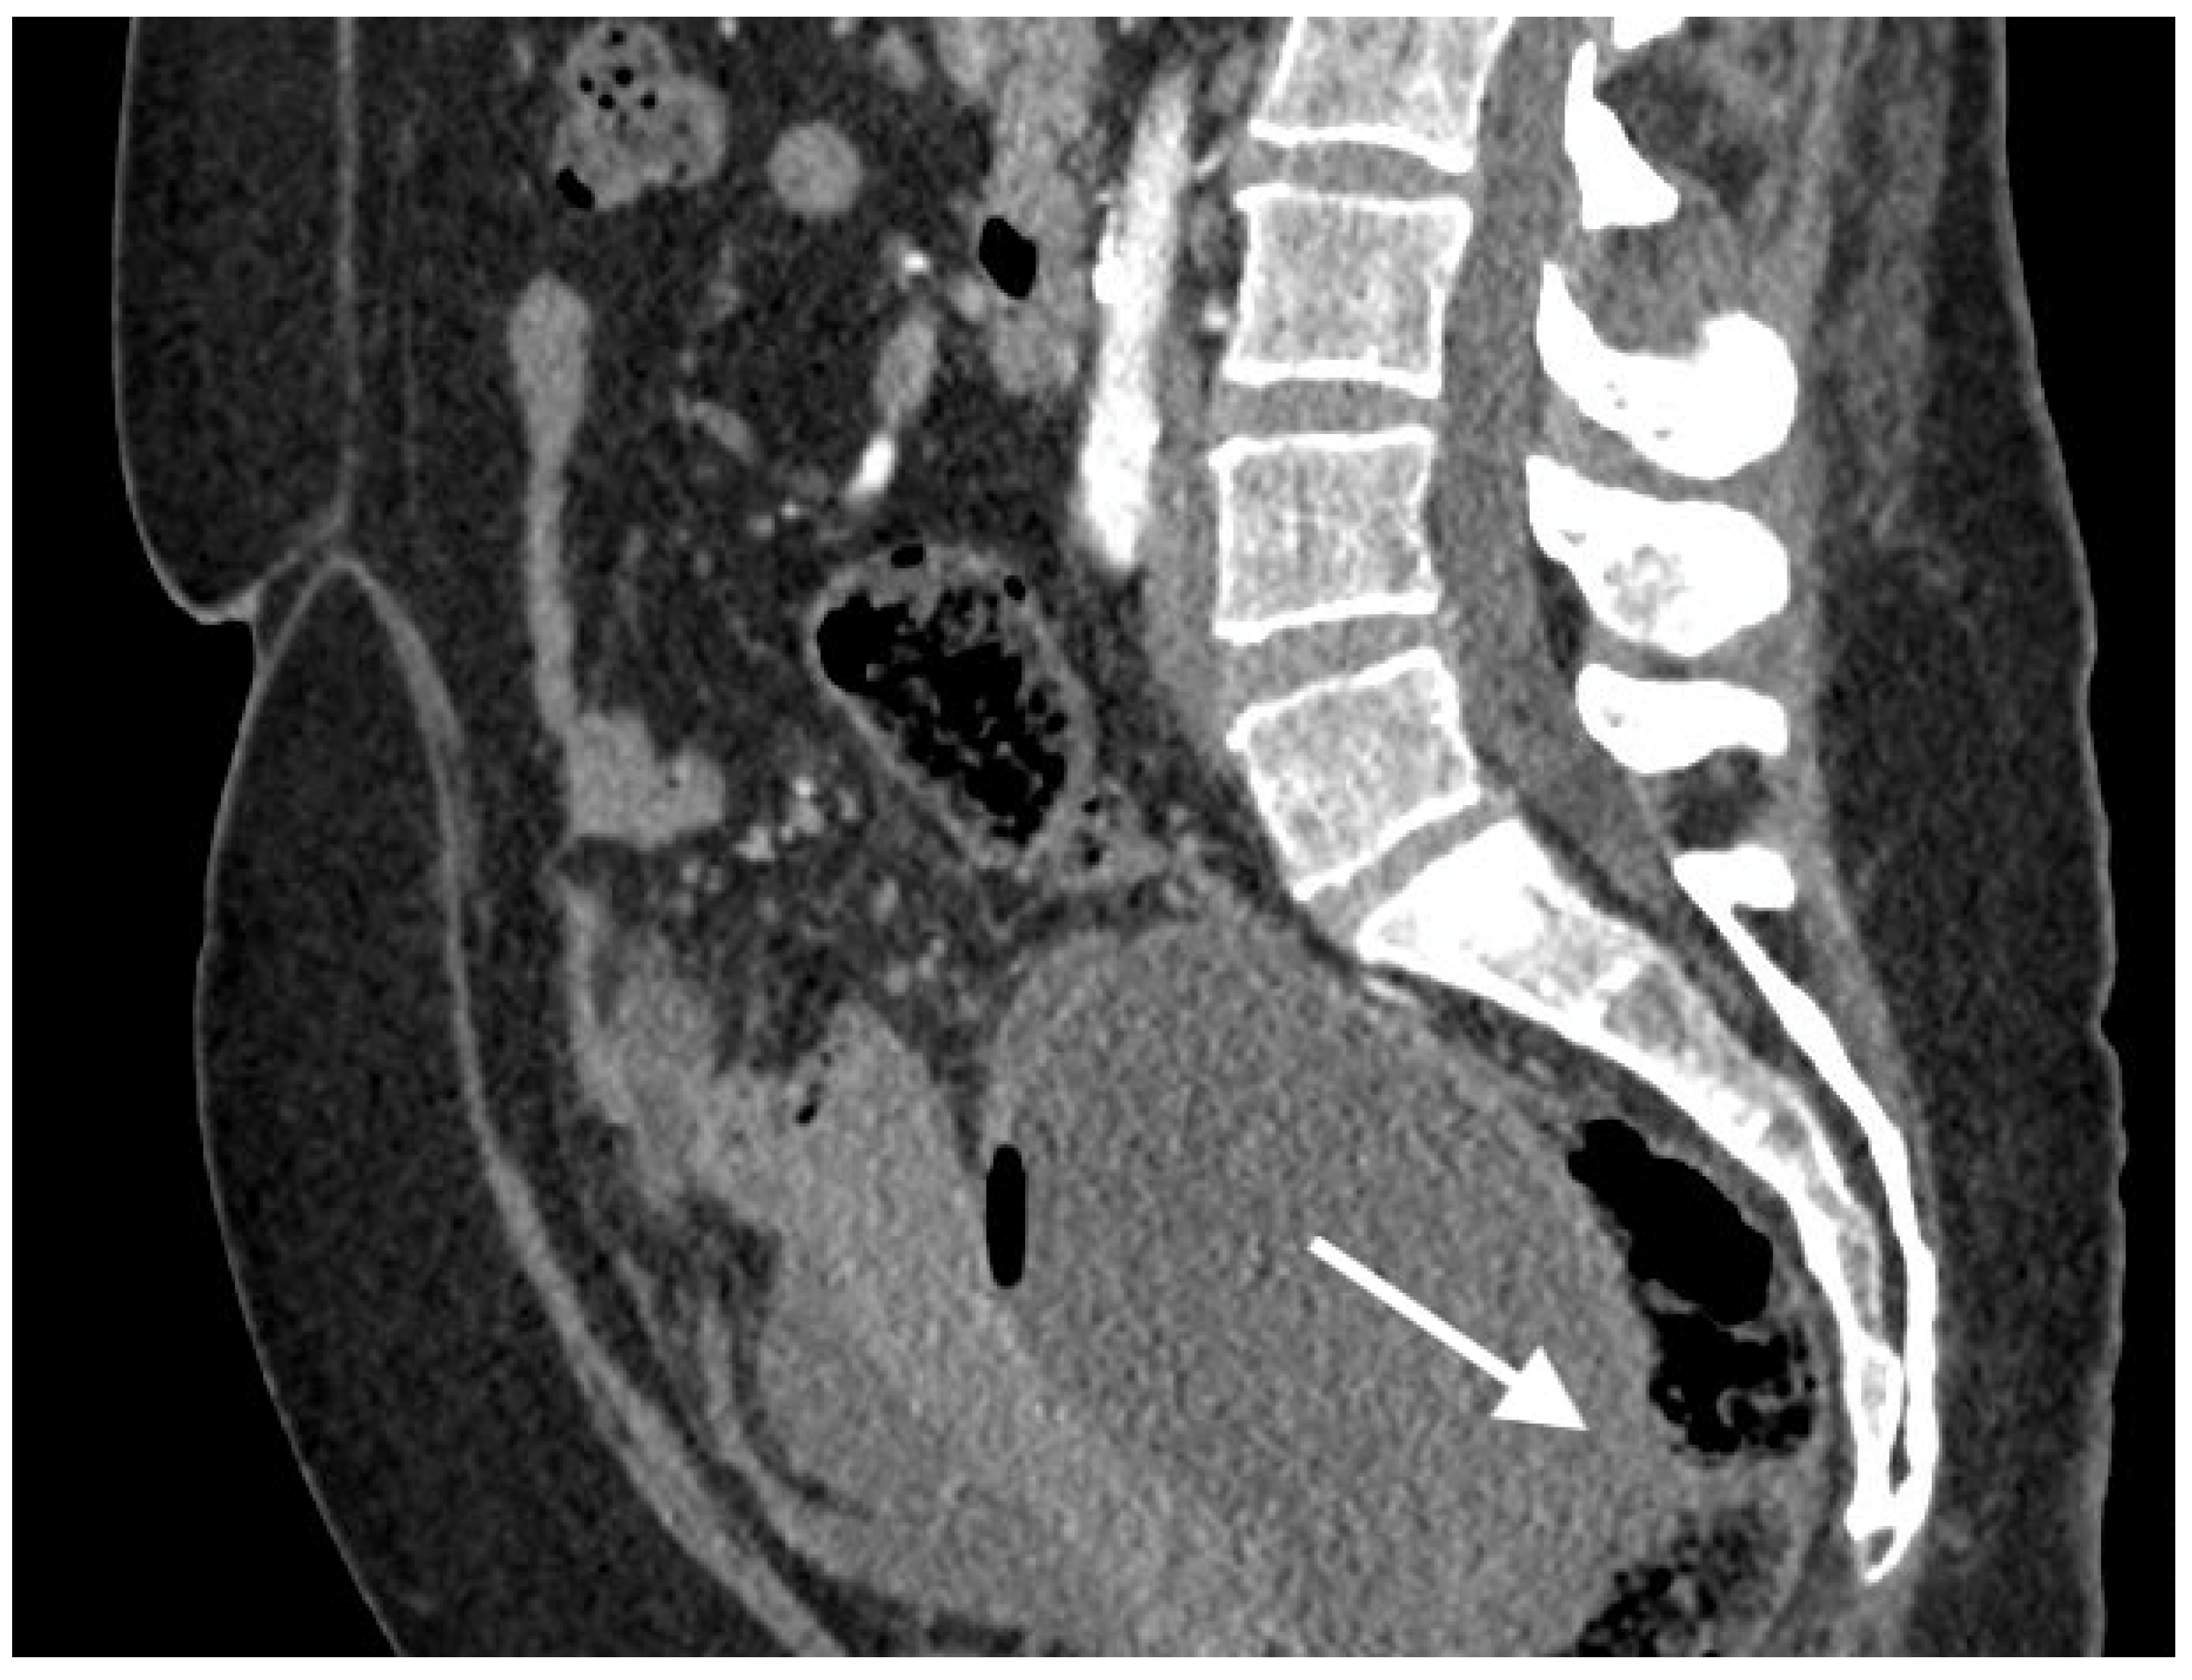

Figure 5.

Images of a 67-year-old woman with a recurrent high grade serous ovarian cancer. MRI T1-weighted post-contrast image obtained in the axial plane (A), coronal plane (B), sagital plane (C), and T1-weighted image post-contrast (D) show large pelvic tumor and fistula (arrows) between the tumor and sigmoid colon.

To confirm the suspected fistula, the patients were referred for MRI. In all cases, the fistula was visible on the MR images, showing hypointensity on the T2 and T1 post-contrast sequences but no restricted diffusion on the DWI sequence. The fistula in one of the patients was hyperintense on T2 images and hypointense on T1-weighted images and showed restricted diffusion on DWI.

Fluid-containing fistulas appear as a high signal on T2-weighted images and STIR, while gas-containing fistulas have a low signal in all sequences and demonstrate contrast enhancement. Old, healed fistulas typically demonstrate low T1 and T2 signals without contrast enhancement, reflecting fibrosis [19]. Our study showed that fistulas were hypointense on T2 sequences and hypointense on T1 sequences, and the best sequences to diagnose fistulas on MRI were T2 sequences and late arterial phase post-contrast T1 sequences, which suggest no active inflammatory processes or necrosis.